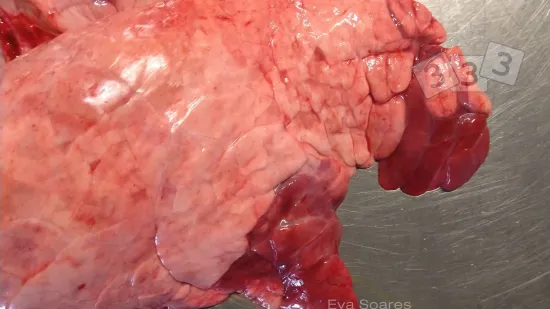

À l'abattoir, la présence de zones rouges de consolidation cranio-ventrale (hépatisation) a été détectée dans ce poumon, suggérant une pneumonie enzootique. Quel est l'agent principal associé à cette condition ?